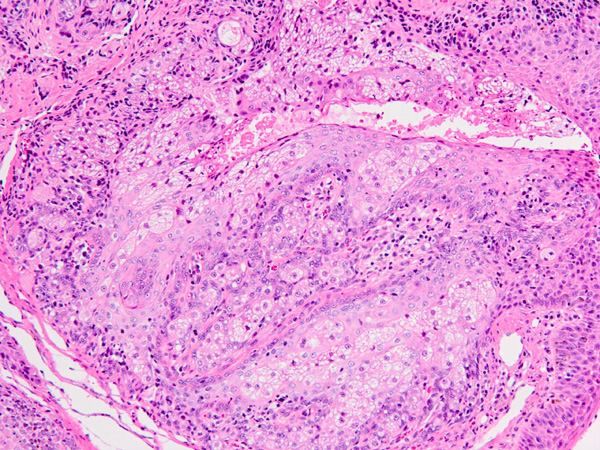

加齢に伴って、まぶたにシコリができることがあります。眼球に対して刺激になって結膜炎や痛みの症状が出る、視覚の妨げになるなどの場合には手術をおすすめします。再発のないようにイボを根っこから、ノッチができないよう「楔形」や「四辺」をイメージに切り取って縫い合わせます。アイラインが確実にピッタリ合うように丁寧に縫うことが仕上がりの良し悪しを決めます。今回の子は病理組織検査の結果「マイボーム腺腫」でした。